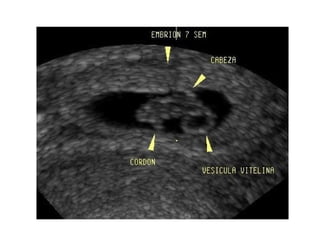

Medición del embrión: LCC

Aumenta su tamaño 1 mm/dia

ECOGRAFIA DEL EMBARAZO INTRAUTERINONORMAL LONGITUD CRANEOCAUDAL. Es posible visualizarlo vía transvaginal a partir de la semana 5. POR VIA TRANSABDOMINAL A PARTIR DE LA SEMANA 6

ECOGRAFIA DEL EMBARAZO INTRAUTERINONORMAL LONGITUDCRANEOCAUDAL Durante la semana 6, con el plegamiento ventral de los extremos craneal y caudal cambia de un disco aplanado a una estructura en forma de “C”.

Medición del embrión:LCC Aumenta su tamaño 1 mm/dia